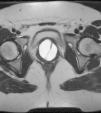

Como pruebas complementarias, se realiza, en primer lugar, una ecografía transvaginal, visualizando un útero en anteversión, de morfología y tamaño normal, con endometrio lineal y anejos visibles sin alteraciones significativas. Al colocar la sonda vaginal sobre el tercio proximal de la vagina, llama la atención, en la cara anterior, la presencia de una masa, redondeada y tabicada, de contenido homogéneo, situada en espacio prevesical, que produce intensa compresión de la vejiga, no llegando a visualizar con claridad si la pared anterior de la misma se encuentra o no infiltrada. La tumoración presenta en su totalidad unas dimensiones de 42,1mm×42,8mm (fig. 1). Se solicita una resonancia magnética (RM) para completar el diagnóstico, que informa la masa como quística compleja, situada entre la vagina y la uretra, con íntimo contacto también con el suelo vesical sobre el que realiza impronta, con unos diámetros en corte axial de 3,8×4,1cm y craneocaudal 3,8cm, interior de contenido quístico, varios tabiques y pequeño nivel líquido-líquido o detritus en su porción más declive. Las figuras 2 y 3 muestran la tumoración visible en resonancia magnética nuclear, que, por sus características radiológicas, es compatible con quiste del conducto de Gartner (siendo siempre un diagnóstico radiológico o de sospecha ya que dependemos de la confirmación anatomopatológica), las indicaciones anteriores forman parte del informe realizado por los radiólogos que realizan dicha RMN, indicando descriptivamente tanto morfología de la masa como tamaño y organodependencia.

En segundo lugar, y no menos importante si hablamos del caso que en esta ocasión nos compete, hemos de dar especial importancia a la RM. Estos quistes muestran una intensidad de señal débil en T1 e intensa en T2, cuando se trata de quistes simples. Sin embargo, en los casos de asociación de complicaciones como hemorragia o cuando el contenido del quiste asocia mucina, la intensidad cambia a intermedia-elevada en T18. La RM no solo es importante para la confirmación diagnóstica, ya que ayuda a establecer las características del quiste, sino que también resulta de utilidad para hacer un estudio más detallado, buscando las posibles anormalidades del sistema urinario que asocia esta patología.